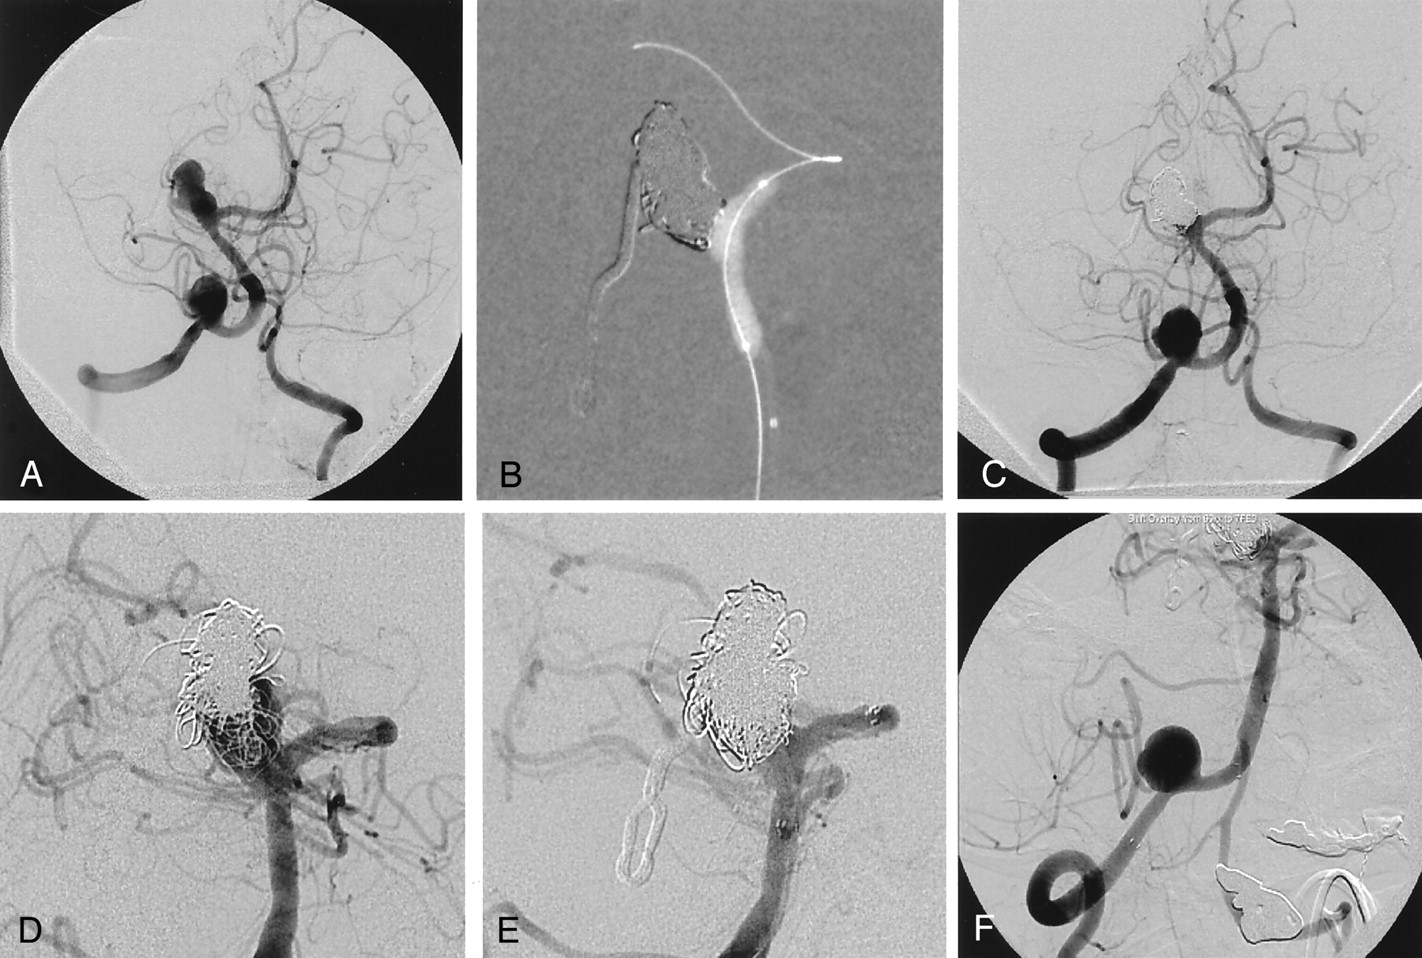

Case 3.

A, Left carotid angiogram obtained after deployment of Neuroform stent shows broad-necked aneurysm originating from the lateral wall of the internal carotid artery at the level of ophthalmic artery.

B, Advancement of the first coil in to the aneurysm through interstices of the stent.

C, Total occlusion of the aneurysm is seen on postembolization anteroposterior left carotid angiography.

D, On lateral view, ill-defined filling defects consistent with significant amount of fresh thrombus is seen within the stented segment of the left internal carotid artery proximal to aneurysm. Partial and complete lysis of the clot is seen on angiograms obtained 15 minutes (E) and 24 hours (F) after starting the intravenous abciximab protocol.